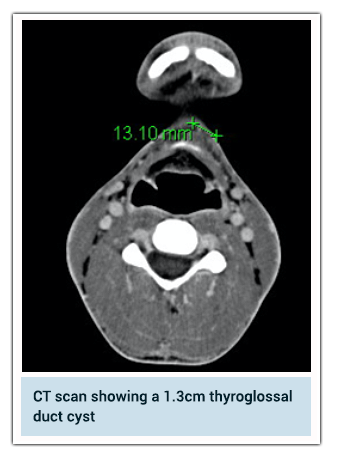

Thyroglossal Duct Cyst

A thyroglossal duct cyst is a pocket in the front part of neck that is filled with fluid. It is formed from leftover tissue from the development of the thyroid gland during embryonic development. The thyroid gland is located in the front of the neck. This has to be investigated frequently with imaging (either ultrasound scan or CT scan) to visualise the location and to ensure it is not the only source of thyroid hormone production in the body. Also a fine needle aspiration cytology can be performed to ensure there is no malignancy.